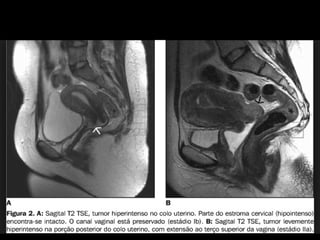

RM SAGITAL T2

TUMOR

DE

COLO

INVADINDO

O

TERÇO

SUPERIOR DA VAGINA.

GEL

ALTAMENTE

HIPERINTENSO

EM

T2

DISTENDE

A

PAREDE

VAGINAL

E

MELHORA

AVALIAÇÃO DA INVASÃO.